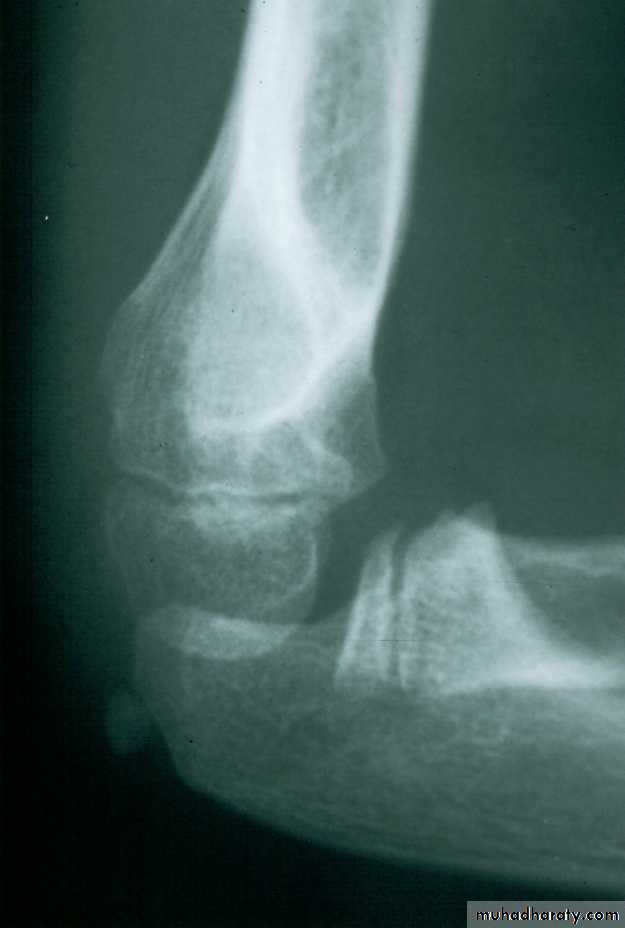

What type of supracondylar fracture

does this patient have?Flex

ionHow do the flexion patterns present?

They present

in the same manner as the extension types.Type I Flexion Injury

550

Tendency toward

valgus alignmentIncrease in the shaft

condylar angle

Because, if the flexion of the condyle is not aggressively

corrected, the elbow may lose extension.

This classical Type III pattern

is obviously a flexion injury.With these one needs to be

prepared to do an open reduction !!